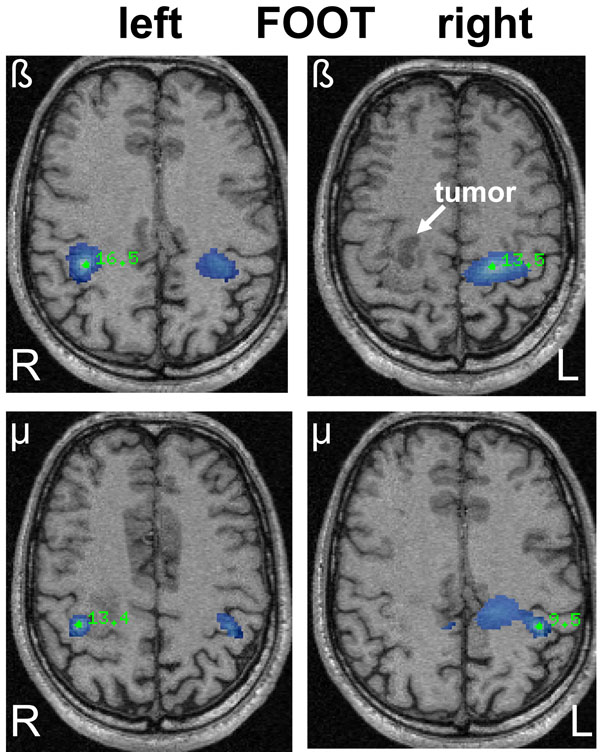

SAM pseudo-T images corresponding to mu and beta ERD associated with left and right sided foot movements in a 42-year old male (patient 16) with a right-sided oligodendroglioma (WHO grade II) in close relation to the precentral gyrus. The ERD areas (blue) show a bilateral and heterotopic distribution for mu and beta rhythms after left-sided (affected) foot movements corresponding to the area of hand representation. Right-sided foot movements show a more diffuse ERD associated with hand and foot representation.

Bilateral beta band activity of the foot (Fig. 2) was found in ten patients, six had left-sided and four had right-sided lesions. The four patients with ipsilateral beta responses of the foot were evenly distributed between left- and right-sided lesions. From the four patients with clinical motor deficits, only one had ipsilateral mu and beta band activity. In general however, ipsilateral mu and beta band activity was more frequently associated with a motor task of the affected hemisphere (Fig. 3).